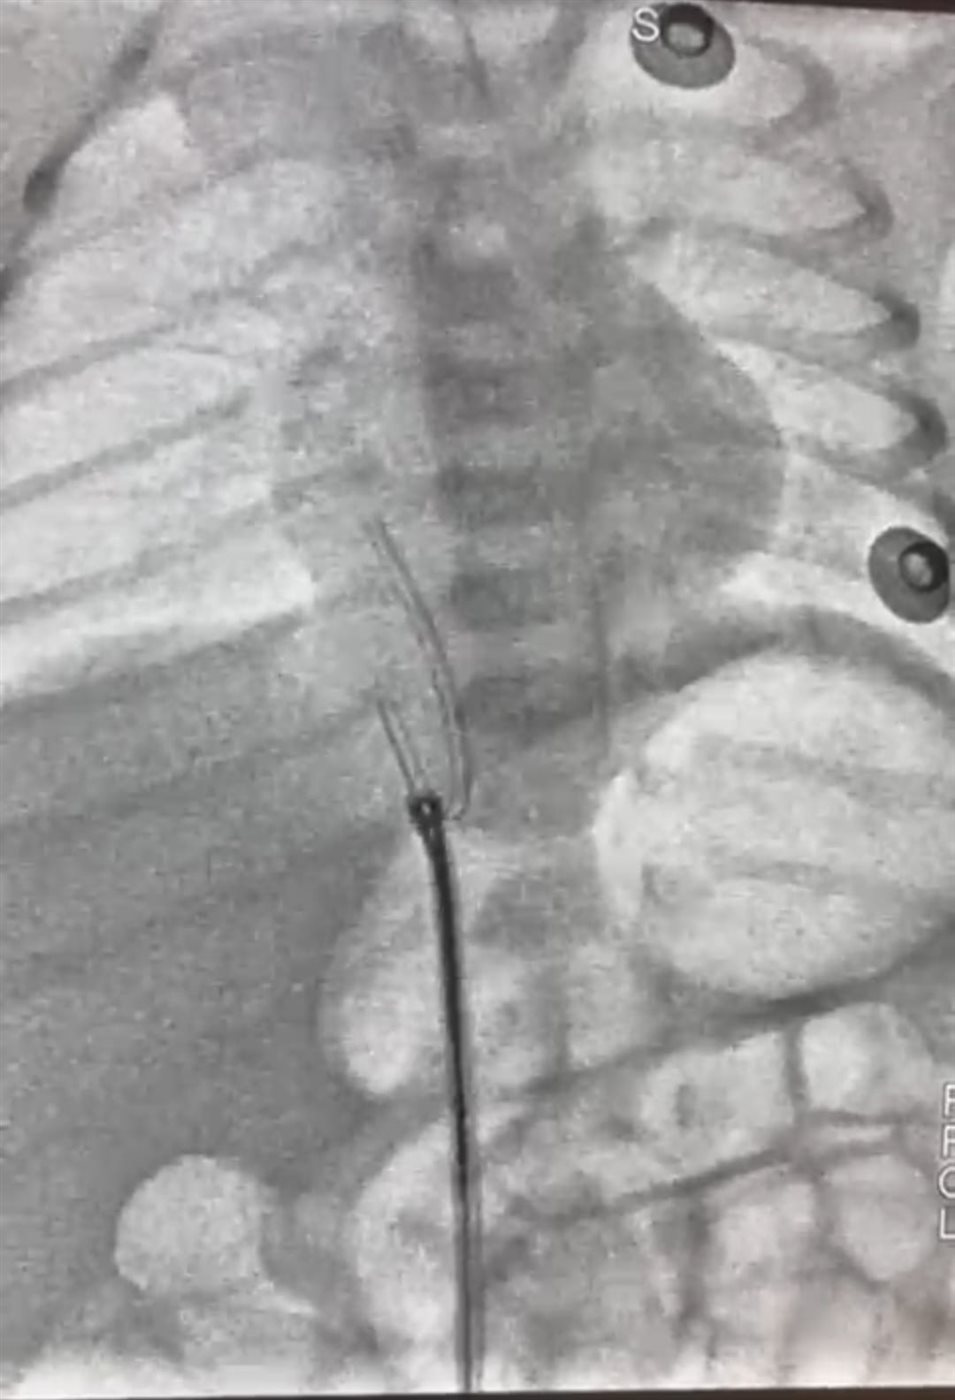

وأفاد أ. د. محمد عبد الهادى.. عميد معهد القلب القومى بأن طفل حديث الولادة، يبلغ من العمر ٥ أيام فقط، قد وصل إلى المعهد في حالة حرجة، بعد أن تحرك جزء من قسطرة السرة من مكانه واستقر في قلب الطفل، وهذه القسطرة تستخدم أحياناً لإدخال السوائل والأدوية، وقد استدعت هذه الحالة تدخلاً سريعًا ودقيقًا، وعلى الفور قام فريق عمل الحضانة، وعلى رأسهم الدكتور/ محمد سعد سلطان.. زميل الأطفال، فى التنسيق لدخول الحالة أول أيام العيد وتجهيزها للتدخل الجراحى، وقام فريق طبي متميز بإجراء القسطرة العاجلة للرضيع. وبفضل الله ومهارة الفريق الطبي، تم استخراج قسطرة السرة بنجاح ودون مضاعفات، والرضيع الآن في حالة مستقرة، وقد غادر الحضانة إلى منزله في حالة جيدة وبدون أي مضاعفات.

وأضاف عميد المعهد أنه ساهم في هذا الإنجاز الطبي فريق متكامل من الأطباء والتمريض والفنيين من أبناء المعهد تحت قيادة أ. د. أحمد معوض الإمام إستشارى القلب وقسطرة العيوب الخلقية بالمعهد، وأ. د. رشا حسني.. رئيس قسم التخدير، وأ. د. أحمد جمال ندا.. زميل التخدير، د. هبة وشاحى .. استشارى الحضانات والرعاية، ود. أحمد أبو هاشم ود. محمود صديق، ود. نعمة إبراهيم، ود. جهاد محمود.